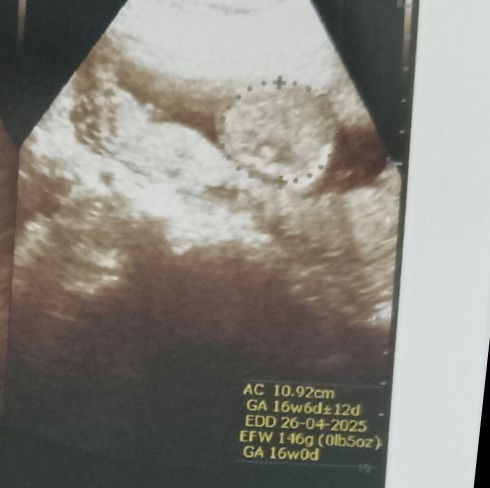

saya baru USG tapi kata dokternya janin saya kecil bun atau bb janinnya kurang jadi ovt bun gmna ya cara naikin bb janin saya pun baru mulai selera makan soalnya usia kandungan 16w berat badan janin baru 146 gram😌😌😔 ada yang punya pengalaman ga bun?? tapi saya liat di apk malah normal bb segitu #Sharing_dong_Bund #bantujawab